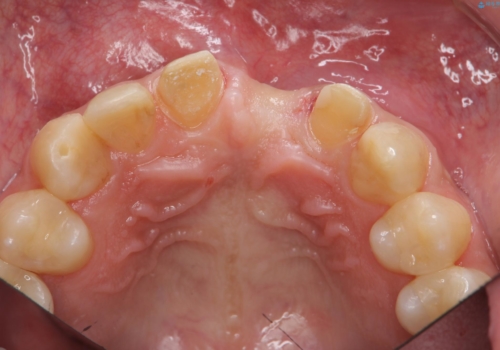

- 以前、前歯にボールが当たりダメになってしまって抜歯したが、そこにとりあえず接着剤で歯をつけて生活していたとのこと。

両側の歯の接着剤の周りが虫歯になってしまっていました。

両側の歯の虫歯をしっかりとってブリッジにすることにしました。

欠損部に長年薄いプラスチックの仮の歯を留めていたため、下の歯が食い込みさらにブリッジのポンティックの隙間がない状態でした。そのため、かみ合わせが深く、下の歯との隙間がかなりなかった為、事前の矯正治療をお勧めしましたが、希望されず特に行わずそのまま虫歯治療を行うことになりました。